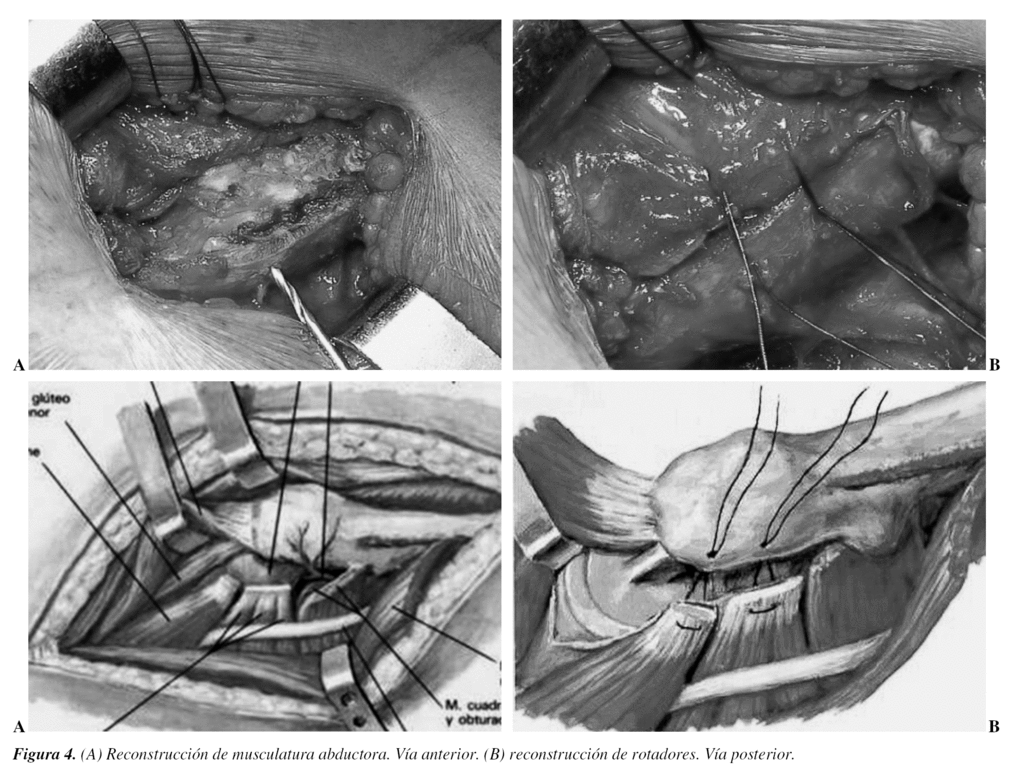

Una de las mejores medidas para prevenir la luxación, que está documentalmente demostrada, es la correcta reparación y cierre de los tejidos seccionados para acceder a la articulación.

En el abordaje posterior cerrar con puntos transóseos la cápsula y los rotadores externos13-15. Si se ha realizado una vía de acceso anterior se debe reconstruir rigurosamente la musculatura abductora (fig. 4). Pero, la mejor recomendación durante la realización de la cirugía es «no salir del quirófano con la más mínima duda sobre la estabilidad de la artroplastia que acabamos de realizar»16.